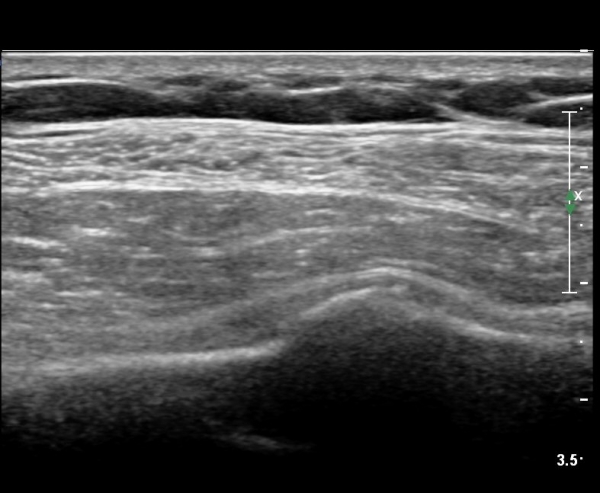

lin longitudinal scan of 7th. rib, appearance of bony mass(protrusion) just like callus(image 1).

on moving of prove a little, there is bony protrusion(osteoblastic lesion) and hypoechoic(osteolytic)  lesion(image 2, 3, 4).

Ultrasonography is very useful for diagnosis of minor or linear fracture of rib.

In minor fracture of rib, doctor can see several phase of findings of rib fracture.

In early phase, doctor can only see  soft tissue swelling(case 1) of minor step of of rib cortex(case 2).

Usually  callus formation  take place 2 weeks after of injury, then   doctor can see bony mass(callus) .

If there is no trauma history  or visualization of callus so ealry , doctor consider the possibility of tumors of rib.

As like this case, visualization of osteoblastic lesion and osteolytic lesion in simultaneously  suggests a malignant mass.